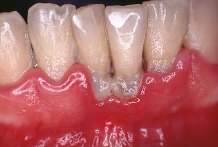

La gingivitis, es la inflamaci�n superficial de las enc�as causada por irritantes de las bacterias presentes en la boca (placa dental o bacteriana), y es com�n en todas las edades, incluyendo en escolares.

Las enc�as que

sangran con frecuencia, lo que se conoce como el famoso "cepillo rosado", es la

se�al m�s com�n que indica que uno padece enfermedades de las enc�as.

Desafortunadamente muchas personas aceptan la situaci�n como normal, debido a que el

desarrollo de la enfermedad es lento y que las enc�as sangrantes causan poco dolor.